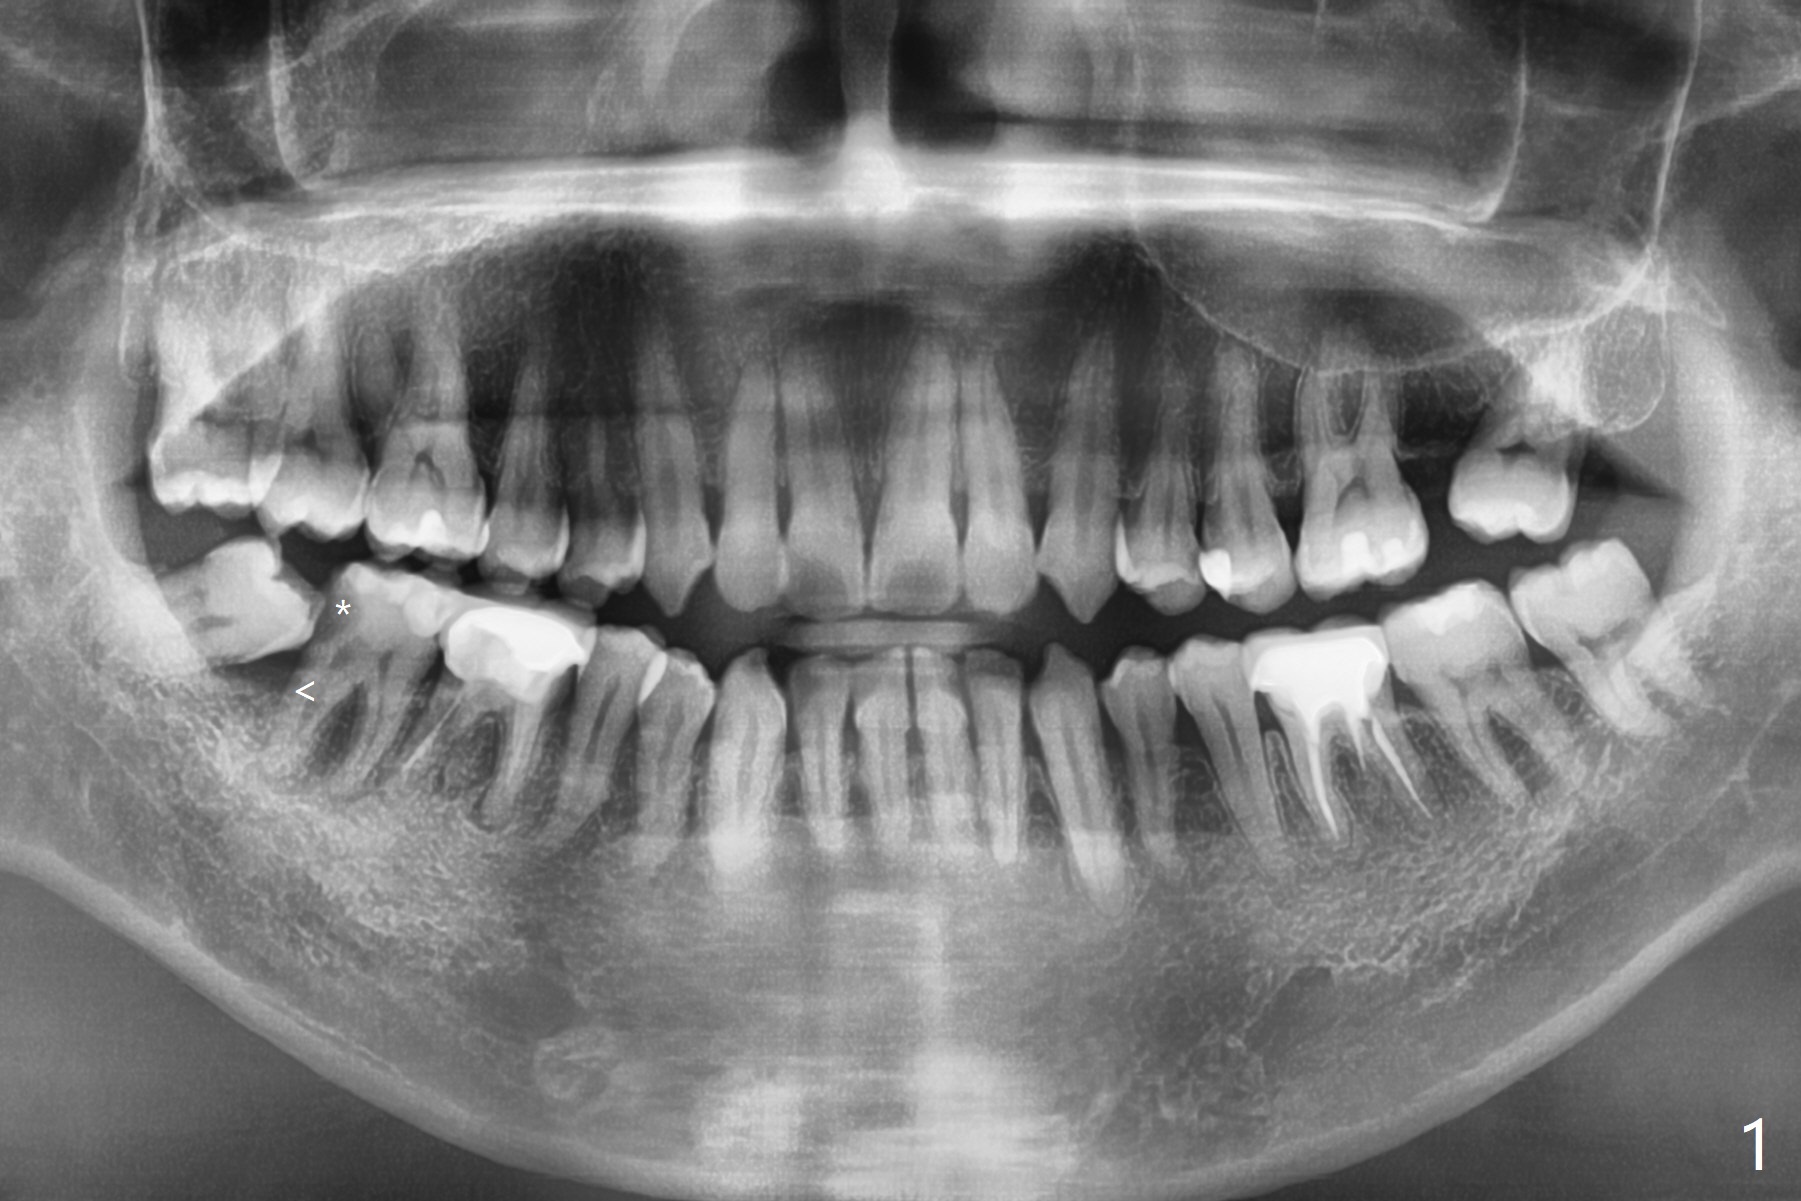

最近放置骨水泥或者胶原塞后连续发生两例干槽症(女51,18岁(去骨))。当57岁男因右下7龋齿夜间痛(图一:*),远中骨质吸收(<)就诊时,提出拔除8后放置粘性骨粉和PRF,他欣然同意。拔除智齿(没去骨,但是劈牙)后,7远中去龋,临时充填(图二:*(IRM,必要时转诊根管治疗))。为了让粘性骨粉在最关键部位(7远中)发挥作用,放置前在牙槽窝根尖放置胶原塞(C),占据空间,后来发现骨粉量足够。